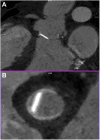

Mechanical valve leaflets have the potential to detach and migrate to unintended locations, leading to life- and limb-threatening situations. We report a unique case of a dislodged mechanical aortic valve leaflet in the right iliac artery bifurcation after a redo mitral valve replacement. This was promptly recognized by input from a multidisciplinary team, allowing immediate correction of the aortic valve insufficiency followed by staged retrieval of the dislodged leaflet to avoid vascular complications. This case highlights the importance of a multidisciplinary team in decision-making and timely intervention. Further research is needed for better understanding of risk factors and prevention strategies.